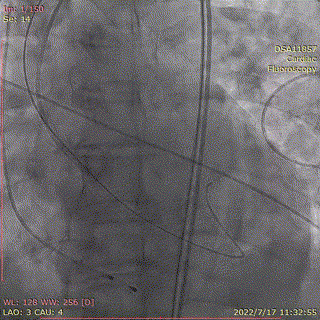

术中首先行冠脉造影术,造影提示右冠近中段严重狭窄,于病变处植入支架一枚。植入后造影显示,无残余狭窄及夹层,前向血流TIMI3级。

冠脉造影,支架植入